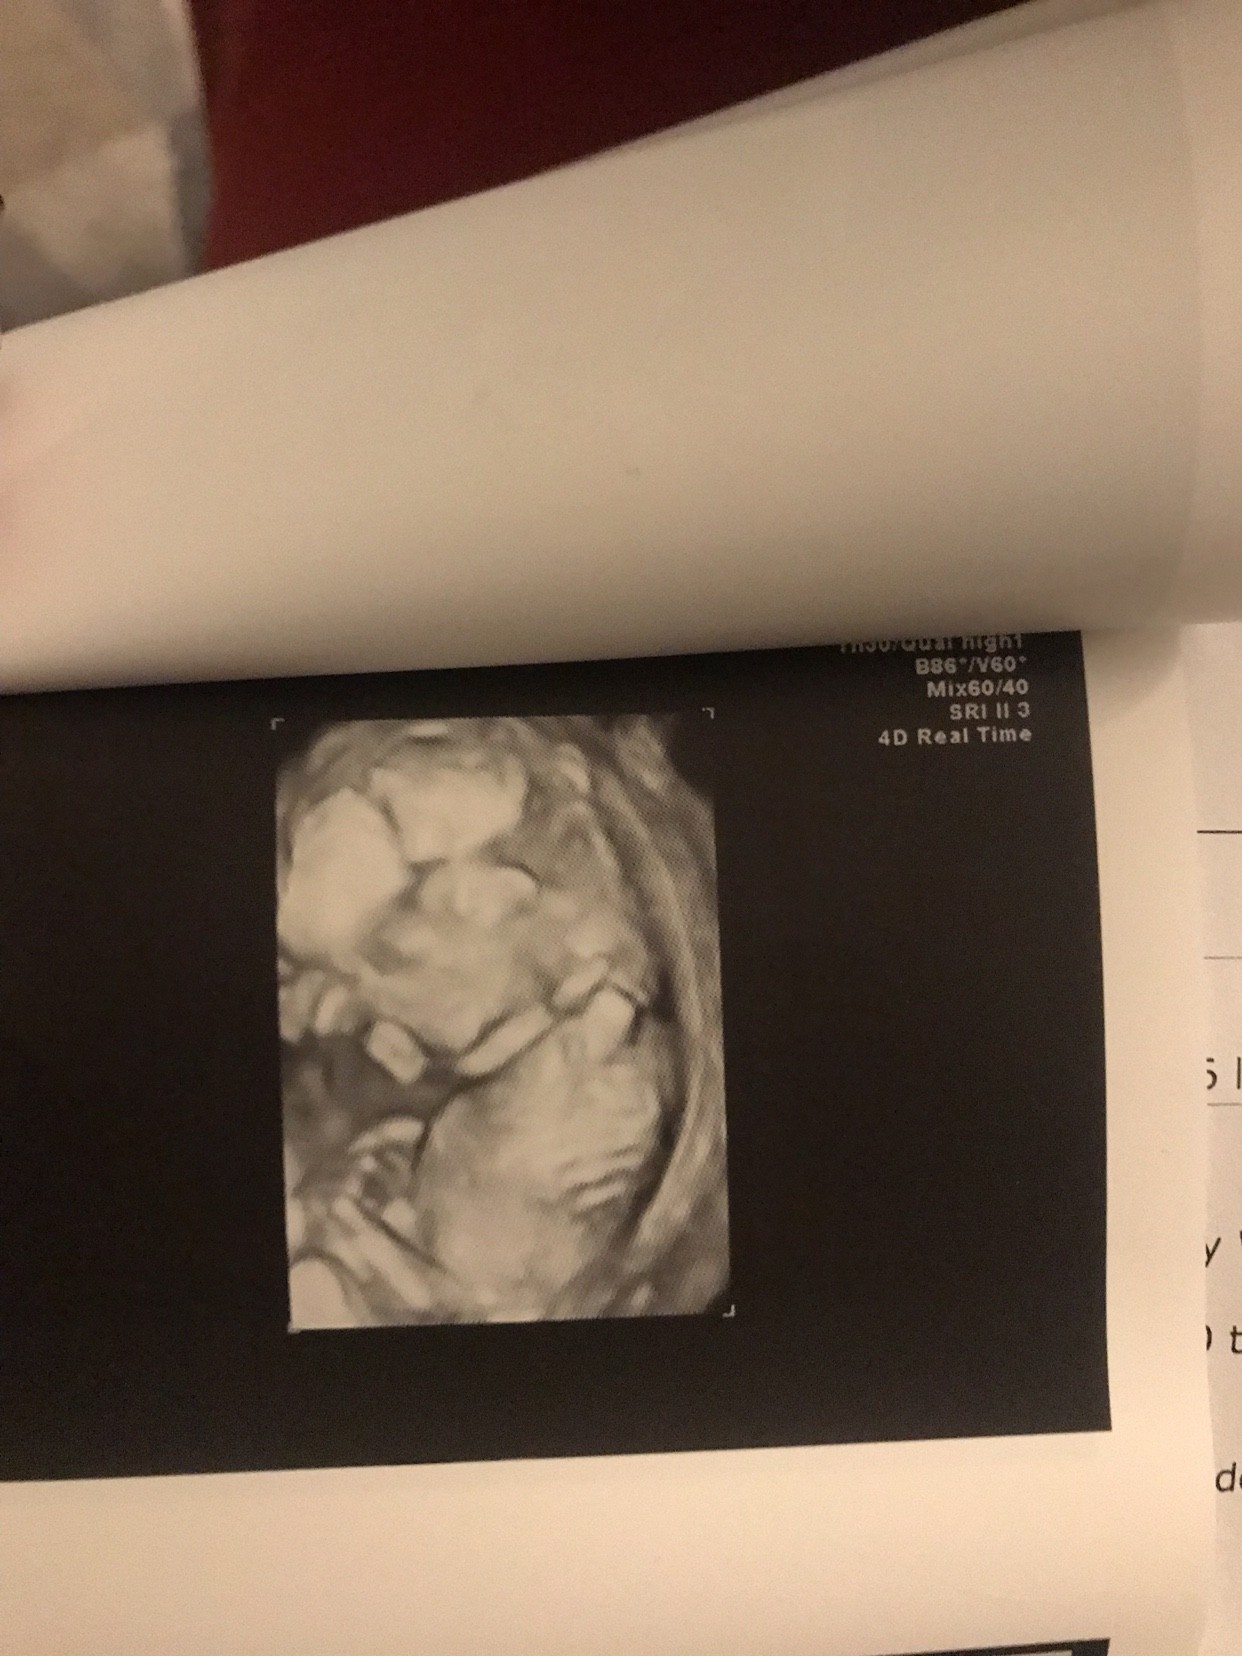

Usg trwało godzinę uparciuch nie chciał się ulozyc odpowiednio do badania [emoji23] wszystkie pomiary ok, wyniki z krwi za tydzień mamy już 5,5cm i Uwaga Uwaga na 70% chłopak!!! Aż nie mogę się otrząsnąć bo cały czas miałam przeczucia ze będzie dziewczyna